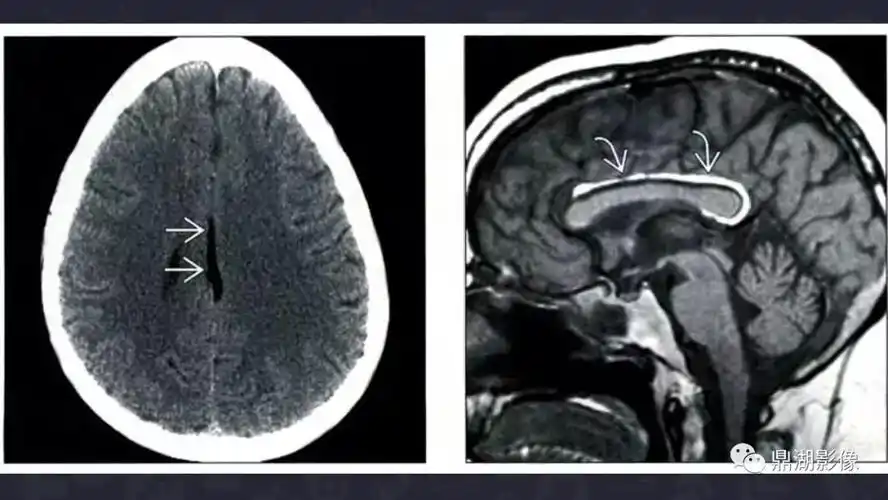

颅内脂肪瘤影像诊断及鉴别诊断

外院检查:报告大脑镰脂肪瘤来我院检查:本院ct:大脑镰钙化经验总结